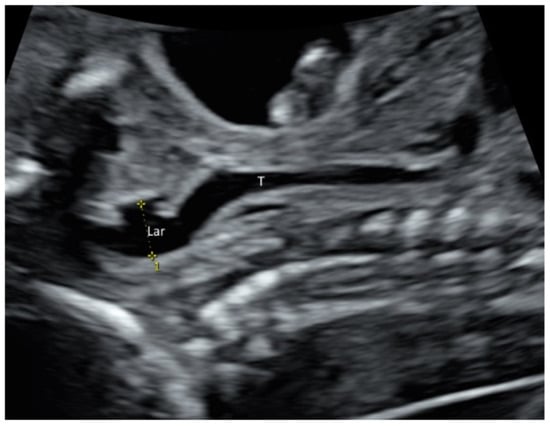

2.2. Face and Neck

- Yu, F.; Leung, K.Y. Prenatal sonographic appearance of laryngeal atresia: A case report. J. Clin. Ultrasound. 2020, 48, 244–246. [Google Scholar] [CrossRef]

- Rogelio, C.M.; Alma, G.V.; Miguel, M.R.; Jonahtan, L.G.; Hugo, L.B.; Eréndira, C.G.; Israel, J.M.; Areli, R.N.; Rosa, V.G.; César, F.H. Prenatal diagnosis of laryngo-tracheo-esophageal anomalies in fetuses with congenital diaphragmatic hernia by ultrasound evaluation of the vocal cords and fetal laryngoesophagoscopy. Prenat. Diagn. 2020, 40, 1540–1546. [Google Scholar]